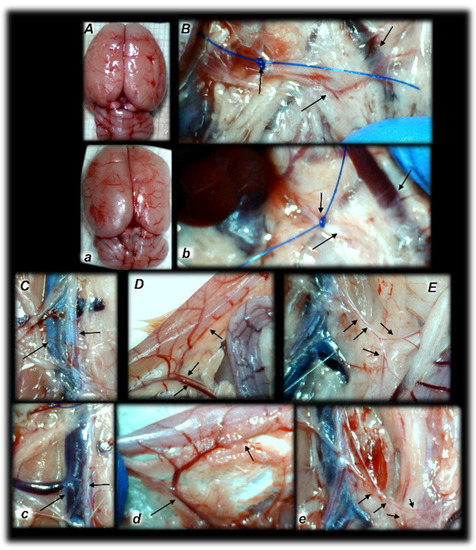

Figure 4. Rats with an occluded superior mesenteric artery and that received saline (small letters, ae) or BPC 157 therapy (capitals, AE) showed quite distinctive presentation of the brain at the end of the experiments (a,A), as well as the superior mesenteric artery (b,B), inferior caval vein and aorta (c,C), inferior anterior pancreaticoduodenal artery (d,D), and inferior mesenteric artery and its ramification (e,E) soon after mediation application. Arrows indicate important points. Arrows show ligation (b,B), and the distal part of the superior mesenteric artery, filled with blood (B) or thin and empty in controls (b), in addition to the superior mesenteric vein, congested (controls, b) and non-congested (BPC 157-rats, B). Arrows show the congested inferior caval vein and thin abdominal aorta (controls, c) and non-congested inferior caval vein and abdominal aorta with a maintained volume (BPC 157-rats, C). Arrows show the congested inferior anterior pancreaticoduodenal vein with no concurrent presentation of the inferior anterior pancreaticoduodenal artery along with the vein, and an apparent gape, and no communication with the superior anterior pancreaticoduodenal artery (controls, d), in contrast to the non-congested inferior anterior pancreaticoduodenal vein with clear presentation of the inferior anterior pancreaticoduodenal artery along with the vein, and clear communication with the superior anterior pancreaticoduodenal artery (BPC 157-treated rats, D). Arrows show the empty and thin inferior mesenteric artery (controls, e), and the inferior mesenteric artery filled with blood and its ramification (BPC 157-rats, E). The camera was attached to a VMS-004 Discovery Deluxe USB microscope (Veho, Denver, CO, USA).

Without therapy, ligation of the superior mesenteric artery rapidly induces peripheral vessels’ failure (proportional with the change of the healthy surface area), and the superior mesenteric vein and inferior caval vein volume immediately revealed a considerable increase, and congestion. Contrarily, the abdominal aorta and inferior mesenteric artery appeared thin. The superior mesenteric artery part proximal to the ligation appeared congested while the part distal to the ligation was very thin (Figure 3 and Figure 4).

Administration of BPC 157 therapy completely reversed the vessel presentation (Figure 3 and Figure 4), as part of the organized bypassing pathways compensating the occlusion of the superior mesenteric artery. The superior mesenteric artery part proximal to the ligation appeared thin while the part distal to the ligation was filled with blood and showed an increased relative volume (Figure 3 and Figure 4). Likewise, the abdominal aorta and inferior mesenteric artery appeared with an increased relative volume. The considerable increase of the relative volume of the superior mesenteric vein and inferior caval was markedly decreased and the volume approached the values observed for the healthy rats.

In addition to the recovered presentation of the superior mesenteric artery, direct recording revealed that only rats that received BPC 157 therapy presented the inferior and superior pancreaticoduodenal arteries along with the vein. Close contact between these arteries may bridge occlusion at the superior mesenteric artery. Similarly, in BPC 157 rats, an inferior mesenteric artery filled with blood with evident ramification (i.e., left colic artery toward middle colic artery) was observed to bridge occlusion at the superior mesenteric artery from the other side (Fisher exact test p ˂ 0.05, at least vs. control).